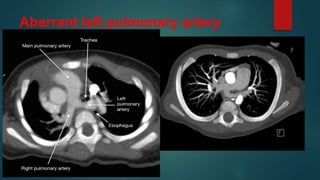

Aberrant left pulmonary artery

• #11 Aberrant left pulmonary artery, also known as pulmonary sling, represents an anatomical variant characterised by the left pulmonary artery arising from the right pulmonary artery and passing above the right main bronchus and in between the trachea and oesophagus to reach the left lung. It may lead to compression and focal stenosis of the trachea Fluoroscopy In most instances, the barium oesophagogram characteristically shows a mass between the trachea and the oesophagus just above the level of the carina, usually seen as an anterior indentation over the oesophagus